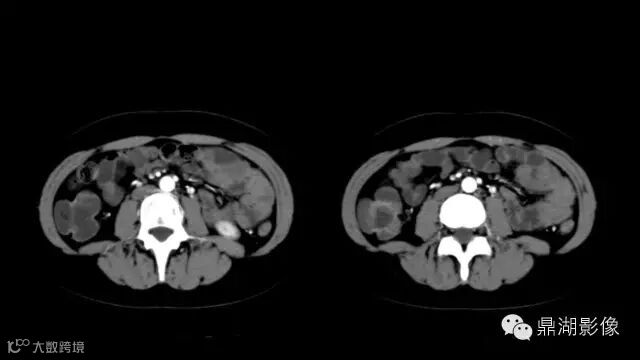

do you know comb sign?

The comb sign refers to the hypervascular appearance of the mesentery in active Crohn disease.

what's the meaning of fat halo sign?

粘膜下水肿或脂肪沉积,可致肠壁内呈低密度层(halo征),其最初用来描述溃疡性结肠炎,是良性肠道病变的结果,无特异性,也可存在于放射性肠炎,移植-受体疾病和慢性缺血性肠炎以及单性的肥胖症患者。

It is the comb sign the most specific sign for crohn's disease.